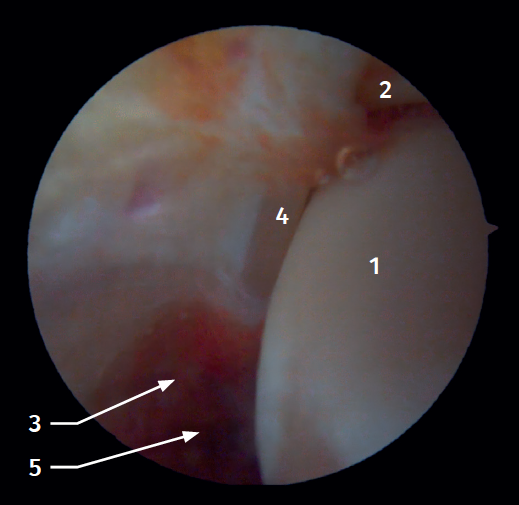

Arthroscopic anatomy of the syndesmosis

Anterior arthroscopic view

Twenty percent of the ATFL is intra-articular(7). On adopting an anteromedial access of the ankle, directing the arthroscope laterally, we can see the distal fibers of the ATFL with their oblique distribution and their continuation with the anterior talofibular ligament (Figure 2). If we move into the tibiotalar joint, we see the distal tibiofibular joint with the syndesmotic recess occupied by synovial tissue (Figure 3).

Posterior arthroscopic view

From the posterolateral approach we identify the lateral (fibular) malleolus and, from here, we visualize the intra-articular fibers of the PTFL, which run obliquely and insert into the distal portion of the tibia. We also see the distal thickening of the PTFL (transverse ligament) in continuity with the posterior lip of the distal tibia (Figure 4).

Arthroscopic anatomy of the medial complex

Arthroscopy allows us to see the deep fibers of the deltoid ligament, corresponding to the intra-articular portion of the ligament. Medial and proximal to the tip of the malleolus we have the insertion of the deep layer of the deltoid ligament. If there is no injury, we will see the anterior portion of the deep tibiotalar fibers. When injury is present, we can visualize the intermediate and posterior portion. The superficial bands, due to their more external location, are not visible by arthroscopy, unless there is no lesion of the deep bands (Figure 5).